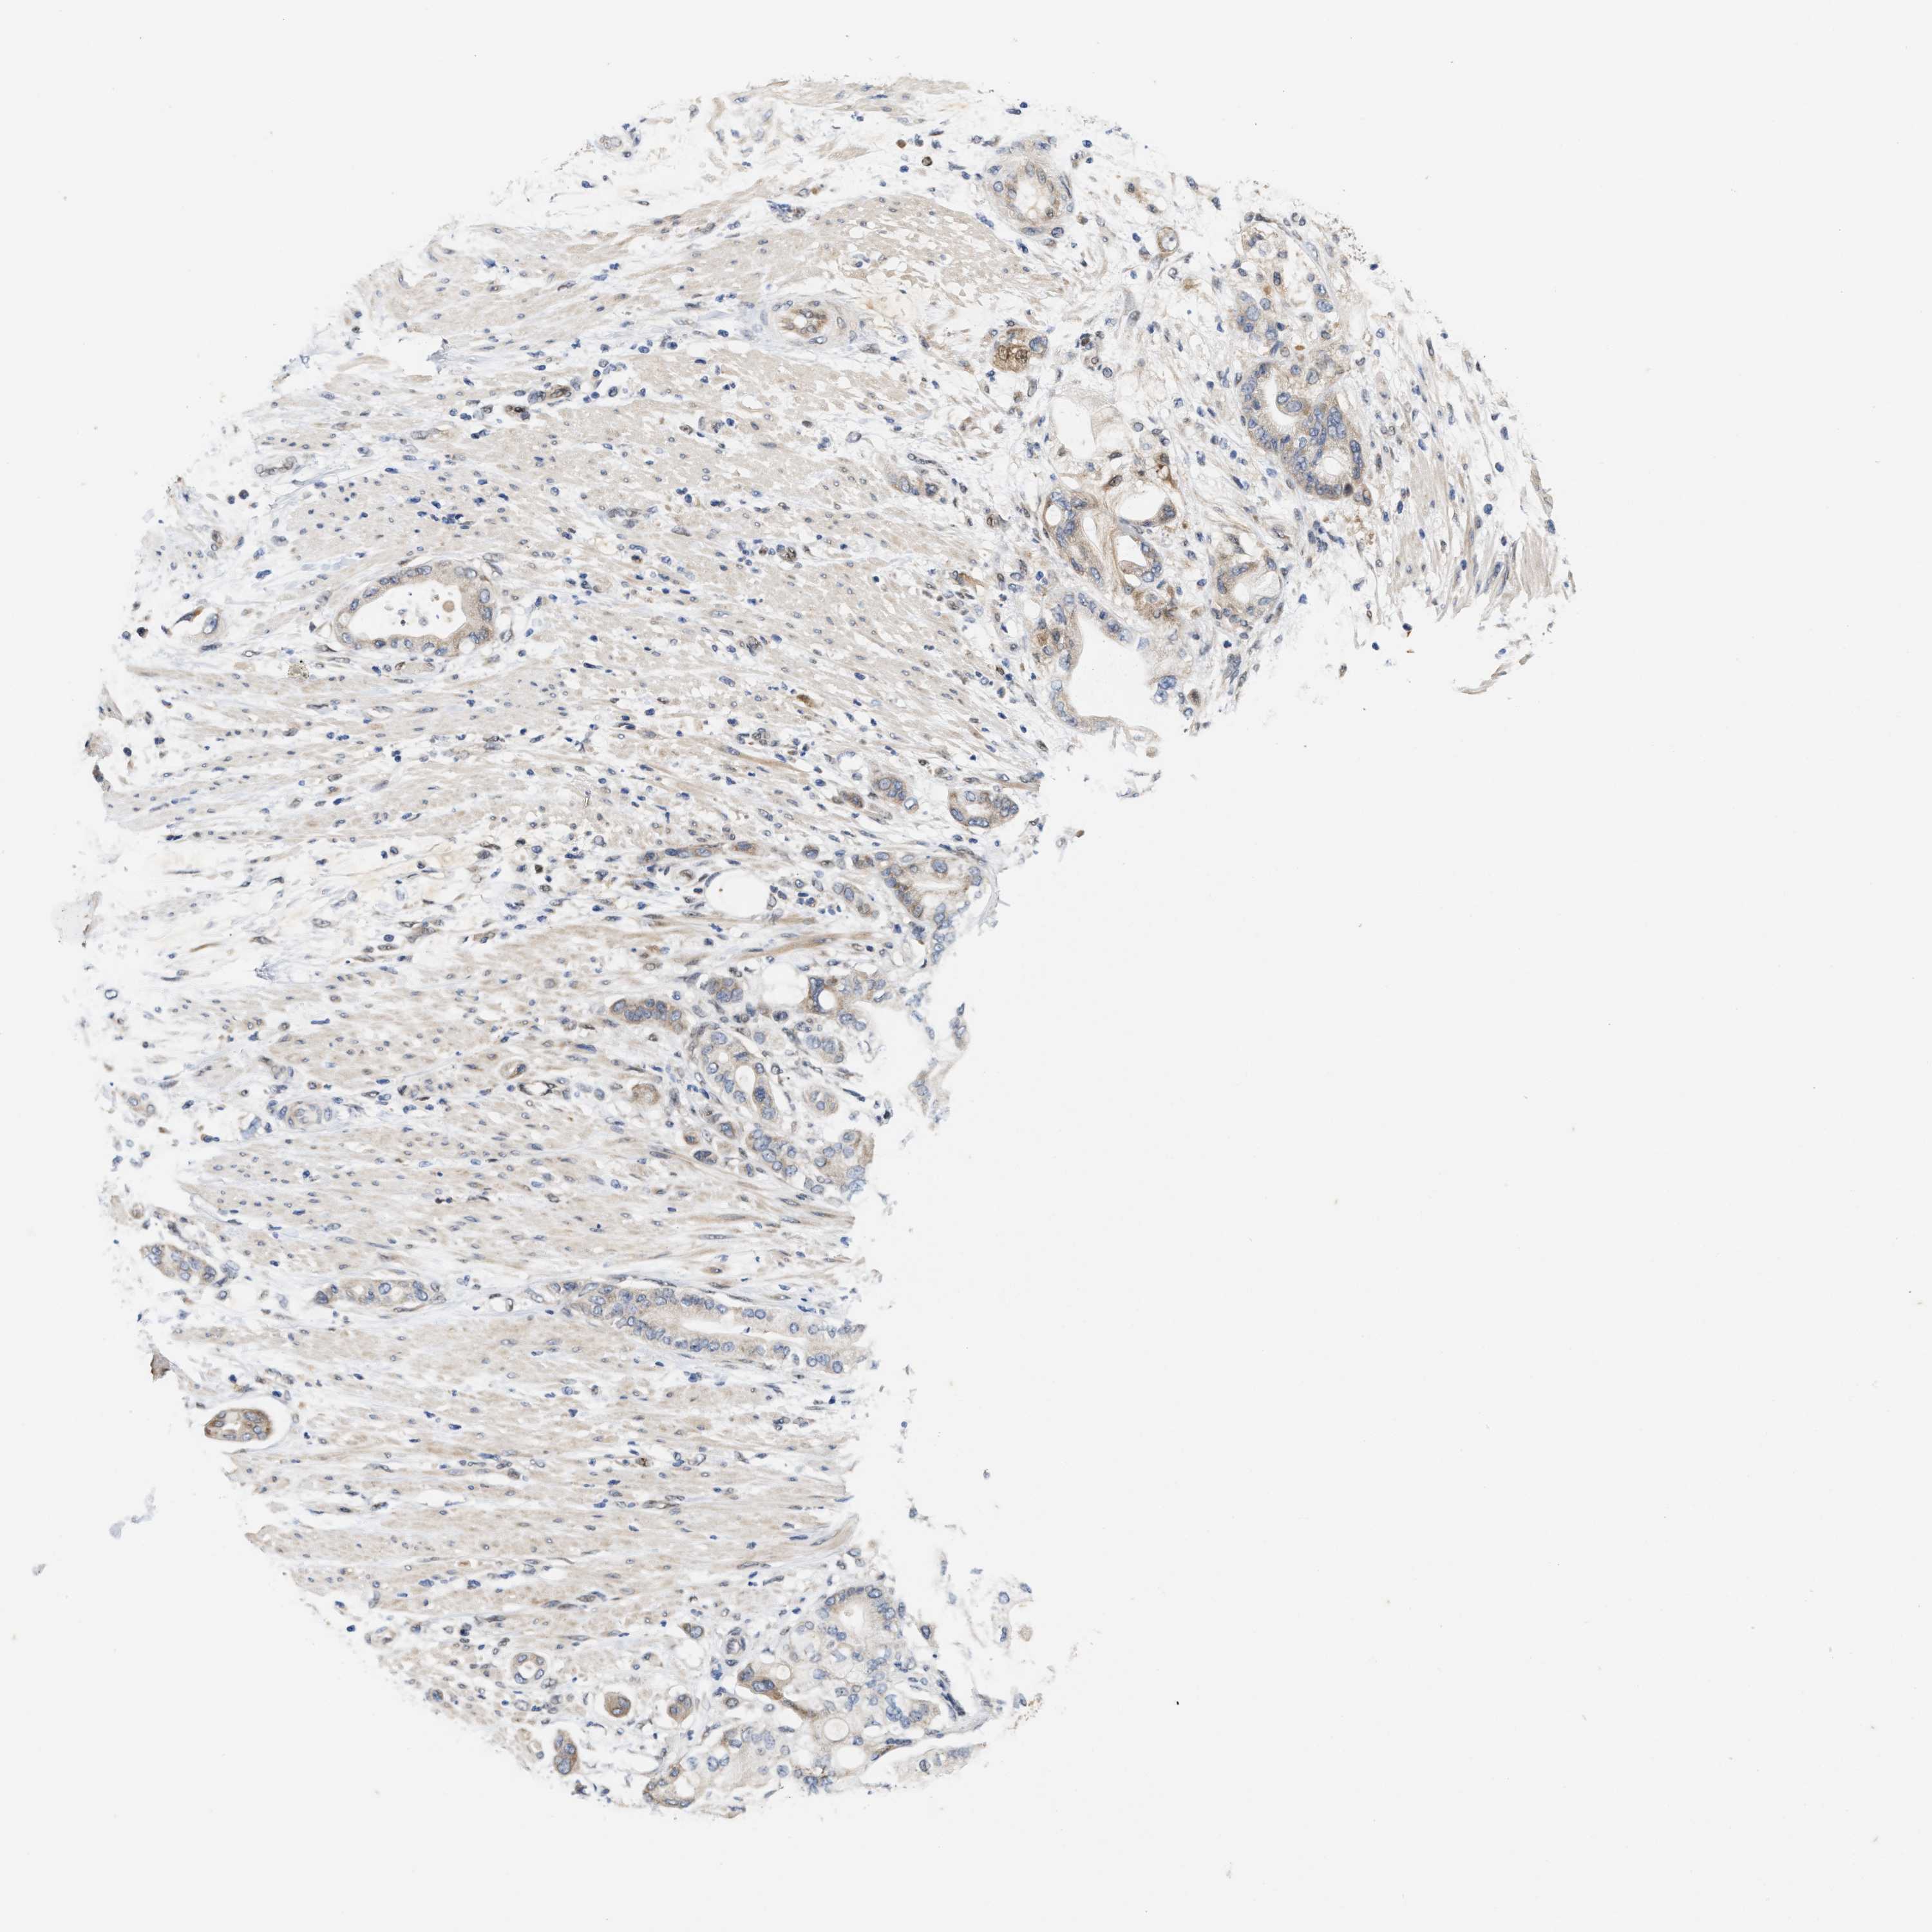

PANCREATIC CANCER - Protein expressioni

A mouse-over function shows sample information and annotation data. Click on an image to view it in a full screen mode. Samples can be filtered based on level of antibody staining by selecting one or several of the following categories: high, medium, low and not detected. The assay and annotation is described here.

Note that samples used for immunohistochemistry by the Human Protein Atlas do not correspond to samples in the TCGA dataset.

Antibody stainingi

Antibody staining in the annotated cell types in the current human tissue is reported as not detected, low, medium, or high, based on conventional immunohistochemistry profiling in selected tissues. This score is based on the combination of the staining intensity and fraction of stained cells.

Each image is clickable and will lead to virtual microscopy that enables deeper exploration of all samples and also displays staining intensity scores, fraction scores and subcellular localization as well as patient and tissue information for each sample.

Antibody HPA025958

Antibody CAB020722

Staining

High

Medium

Low

Not detected

Intensity

Strong

Moderate

Weak

Negative

Quantity

>75%

75%-25%

<25%

None

Location

Nuclear

Cytoplasmic/membranous

Cytoplasmic/membranous,nuclear

Adenocarcinoma, NOS

Adenocarcinoma, metastatic, NOS